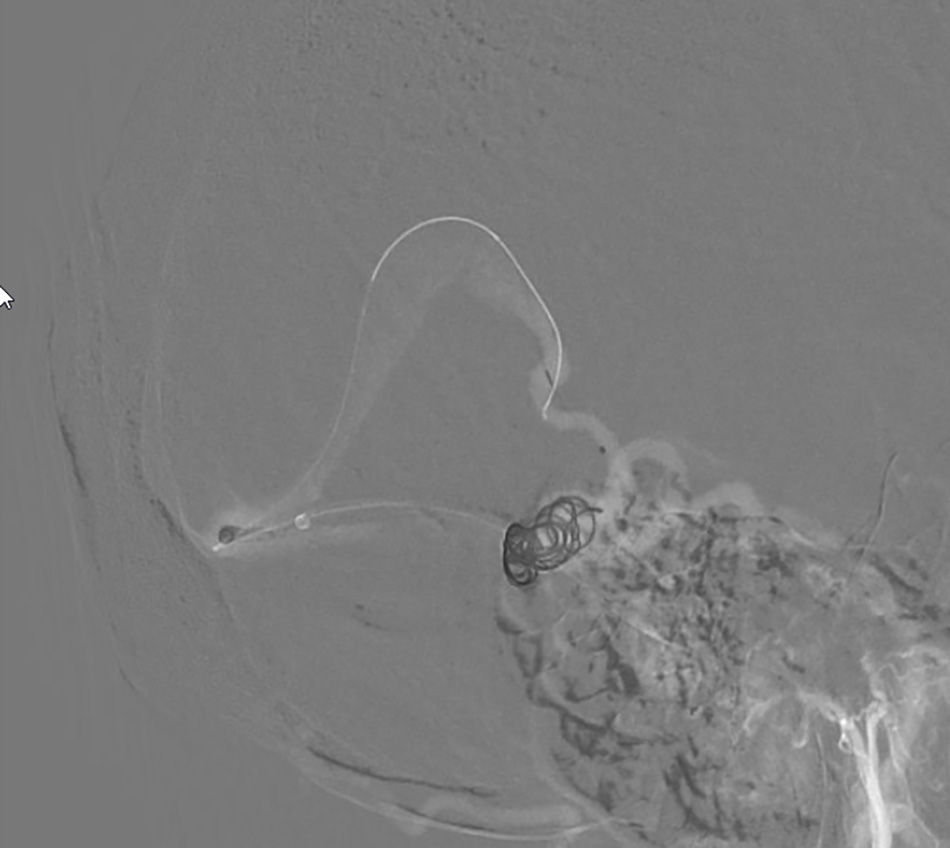

Interventional doctors thread the wire through the cerebral veins and begin deploying metal coils to occlude the aneurysm.

The image shows that the aneurysm has been completely occluded with coils.

Dr Danh explained that due to the aneurysm’s location being difficult to access, he had to navigate the catheter through a vein instead of an artery. “If intervening through an artery is like driving on a smooth, paved road, then intervening through the vein is like crossing rugged, winding terrain, which carries a higher risk of complications,” Dr Danh compared.

Through a small incision in the thigh, Dr Danh carefully guided a catheter and micro-guidewire through the vein to reach the aneurysm in the brain. A total of 12 coils (metallic spiral wires) were placed inside the aneurysm to “patch” the damaged area and block the blood flow through the rupture.